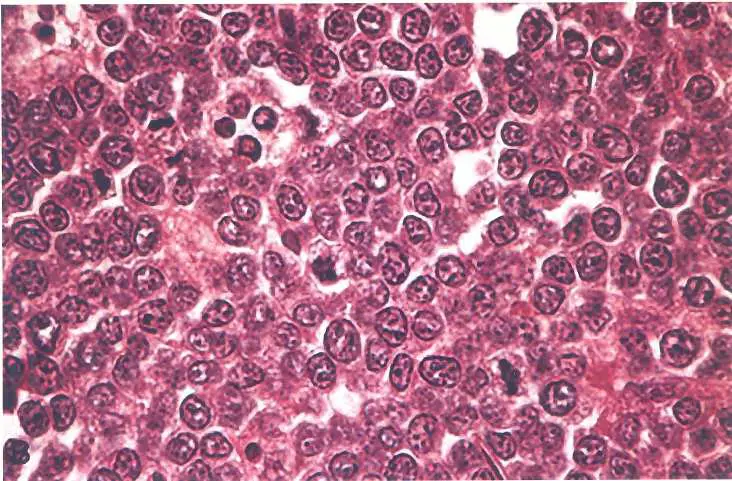

10 歲小孩有一個下頷腫塊。病理切片如圖,腫瘤細胞較小,核不分葉,常見細胞分裂。則下列敘述何者錯誤?

- 顯微鏡下觀察:圖片顯示為高倍率下的組織病理切片(H&E染色)。

- 背景細胞(Sky):視野中充滿了瀰漫性、單一形態的中等大小淋巴細胞。這些腫瘤細胞核圓且深染(basophilic),核仁明顯,細胞質稀少。這構成了深藍色的「天空」背景。

- 吞噬細胞(Stars):在深藍色的腫瘤細胞背景中,散佈著許多胞質淡染、體積較大的組織細胞(Histiocytes/Macrophages)。這些巨噬細胞內含有被吞噬的細胞碎片(tingible bodies,即凋亡的腫瘤細胞核碎片)。

- 特徵總結:這種深色背景中散落淡色細胞的現象,即為經典的 「滿天星」(Starry sky appearance) 形態,是 Burkitt lymphoma 的病理特徵標誌。